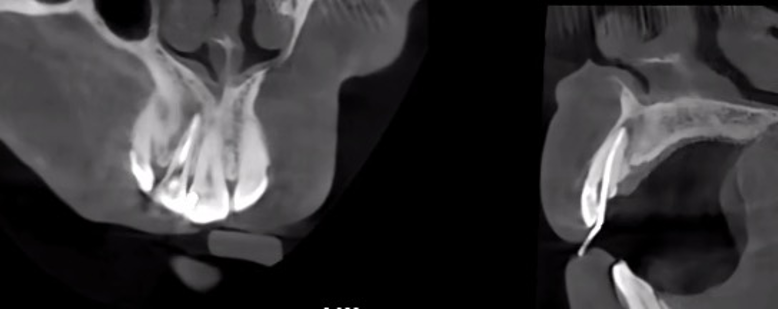

12/29/2024: Follow-up visit: Improved soreness, weakness and softness with mastication. CBCT demonstrated decreased size of apical radiolucency in #12.

The CBCT scans demonstrate the resolution process of periapical inflammation in tooth 12. Over a period of more than four months, the periapical inflammation has essentially subsided, and bone regeneration has initiated in the regions with bone defects caused by the prior inflammation.